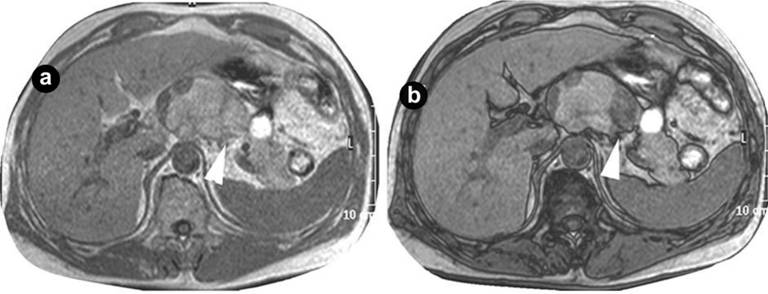

Kudo et al. (2011) recently showed that in-phase and out-of-phase MRI scans can greatly distinguish lymphoepithelial cysts from other cystic lesions of the pancreas, signaling a significant step towards preoperative diagnosis [8]. This novel approach depends on the phase difference caused by the variation in resonance frequency of hydrogen protons in water and fat. A similar intensity between in-phase and out-of-phase is observed if the tissue includes only water or fat. On the other hand, co-existence of water and fat leads to major signal reduction of out-of-phase MRI versus in-phase MRI. The authors observed that in cases of pancreatic mucinous cystic tumors or intraductal papillary neoplasms, there were no differences in intensity between in-phase and out-of-phase MRI scans. However, with lymphoepithelial cysts, a gap of signal reduction was evident between the out-of-phase MRI compared with in-phase MRI, confirming the co-existence of fat and water in these cysts [8] (Figure 2).

|

Figure 2. An image showing in-phase (a.) and out-of-phase (b.) MRI with significant decrease of MR intensity in the lymphoepithelial cyst. (Reproduced with permission from Kudo et al. [8]). |